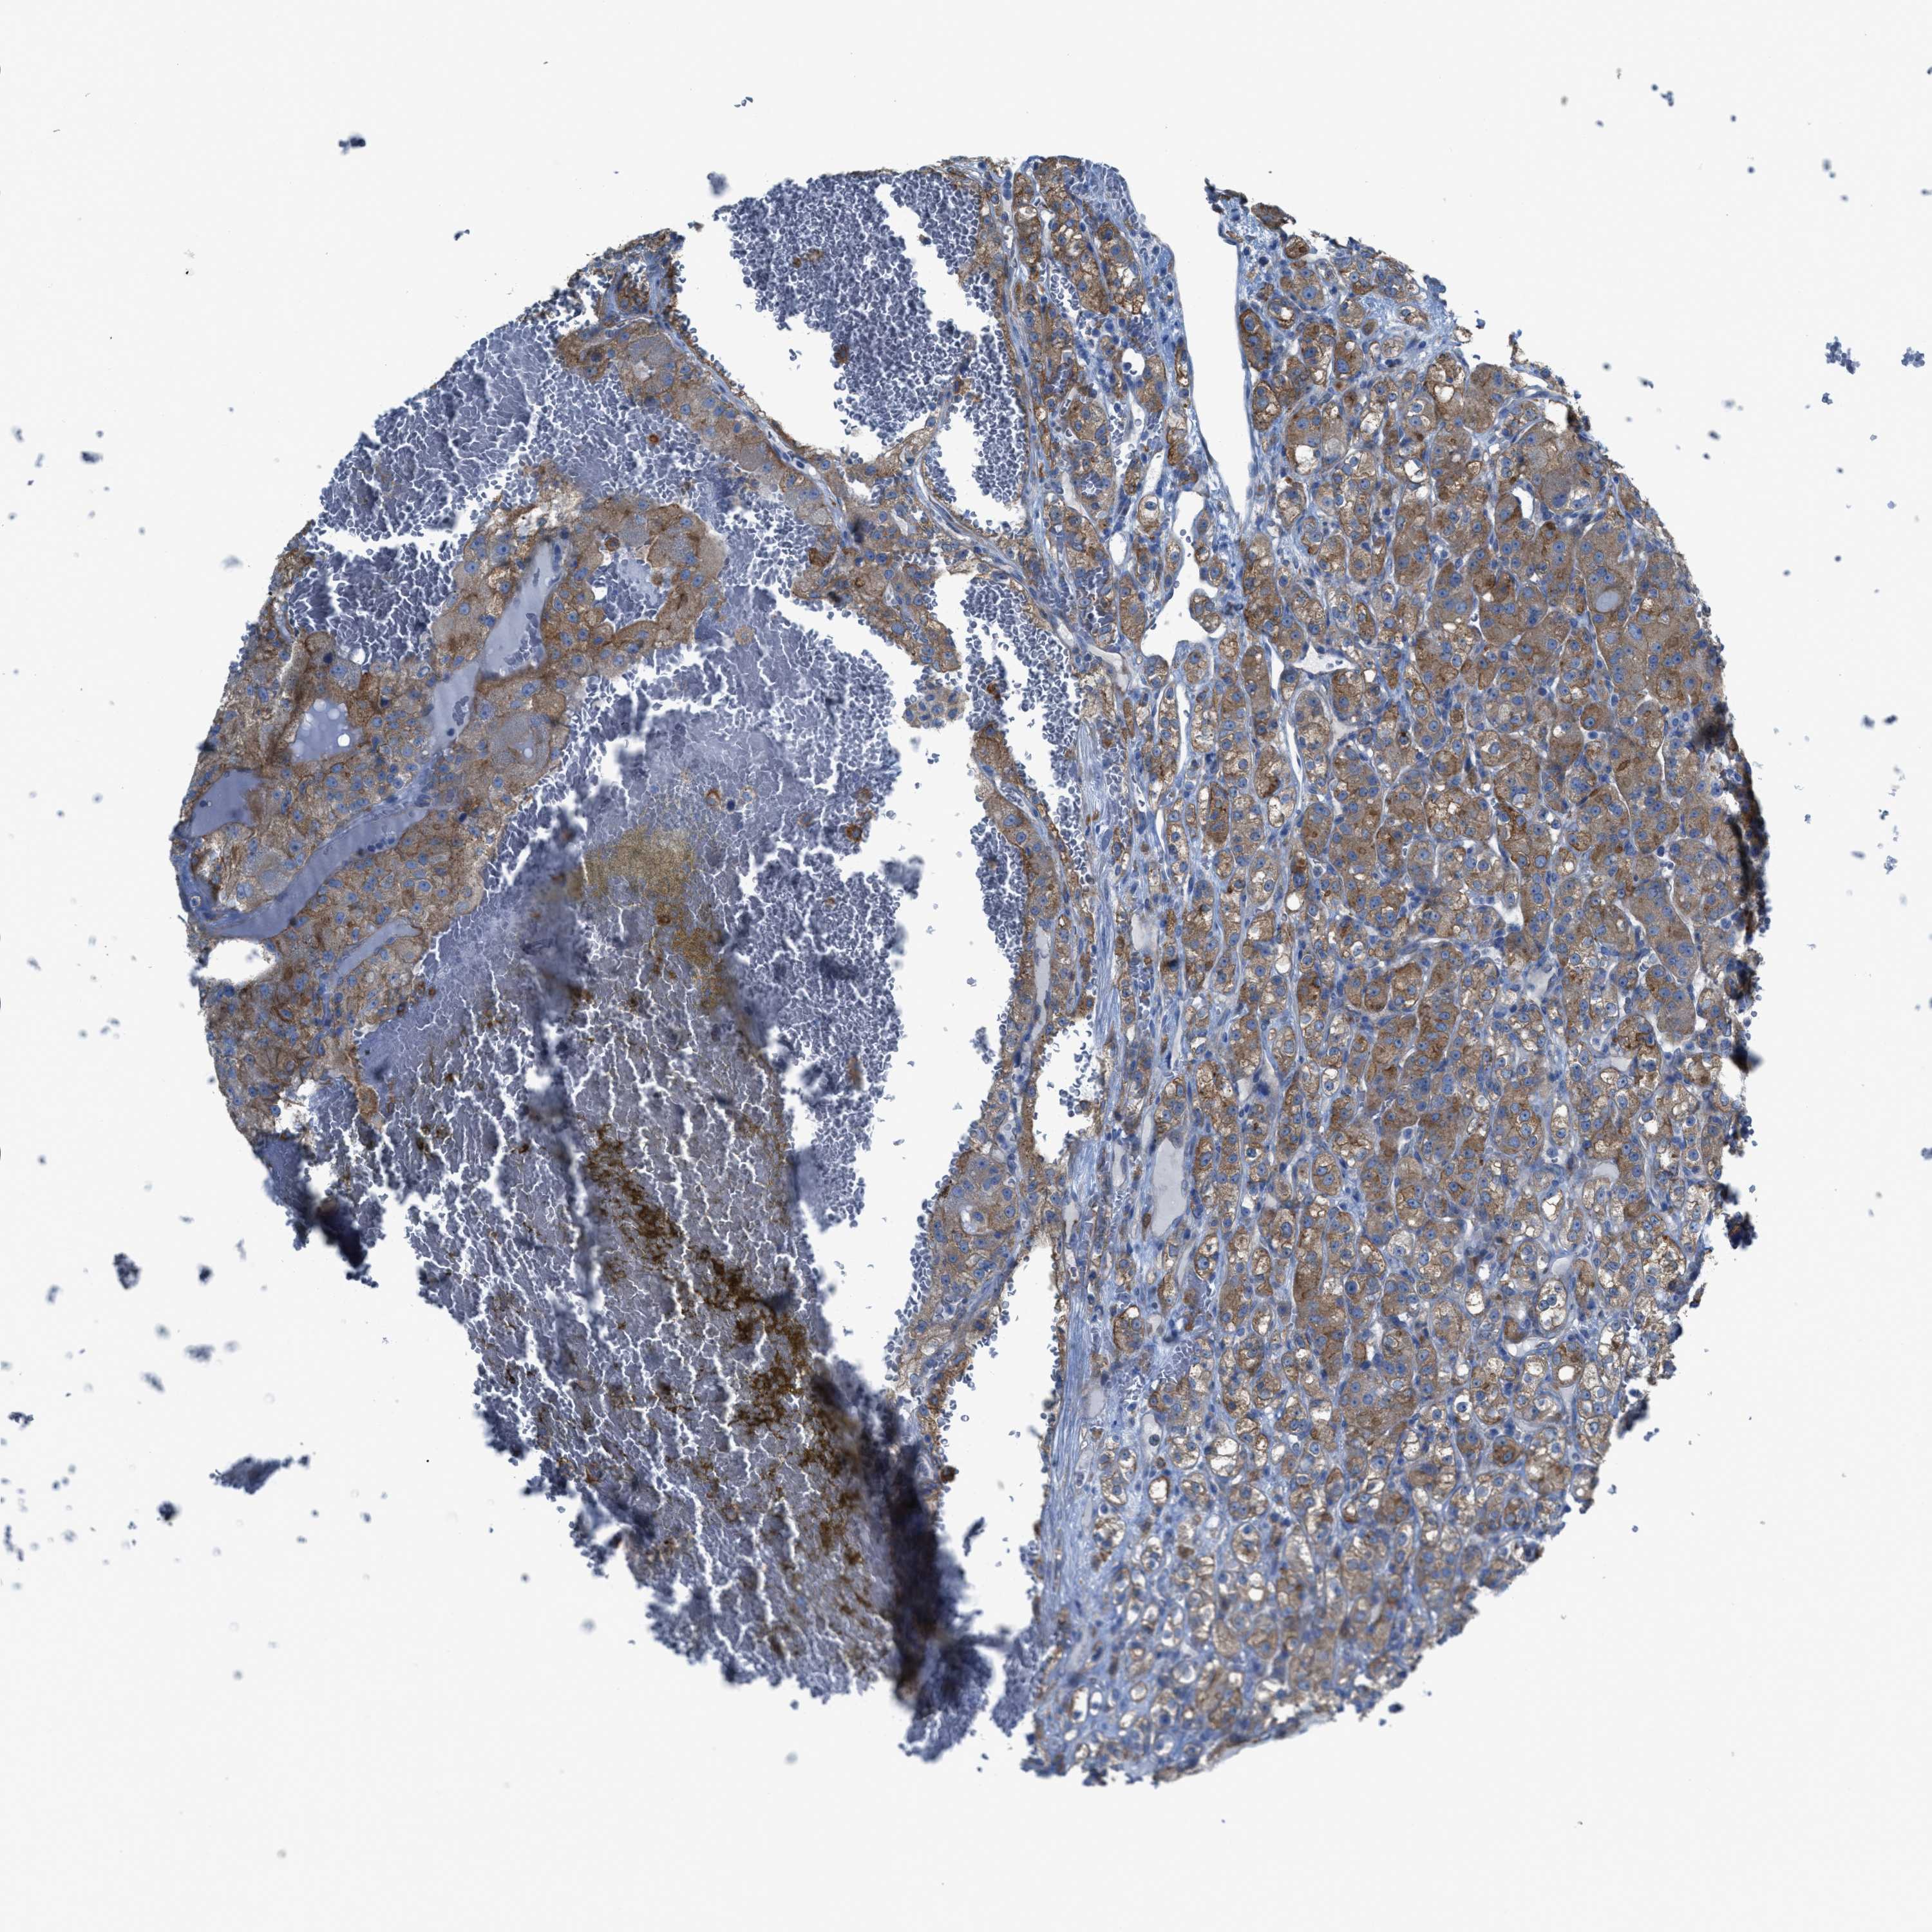

CANCER RENAL CANCER Show tissue menu

KICH TCGA KIRC TCGA KIRC VALIDATION KIRP TCGA PROTEIN RCC CPTAC PROTEIN EXPRESSION